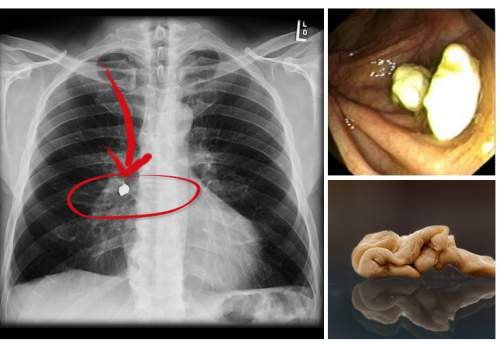

Ainsi, de par sa composition, le chewing-gum peut être difficile à digérer, mais ne colle certainement pas à l’estomac : il sera éliminé par les voies naturelles. En effet, lorsqu’on avale un chewing-gum, il descend directement vers l’estomac, sous la même forme parce que les dents ne peuvent le découper en morceaux. L’étape qui suit est la décomposition des constituants du chewing-gum par les enzymes, et c’est justement là que réside le problème. Notre corps dispose d’enzymes capables de décomposer les glucides et acides que contient cette friandise, mais ne possède pas d’enzymes pour les polymères de la gomme de base. Même les acides de notre estomac ne peuvent le dissoudre, puisque ces substances sont très résistantes. C’est la raison pour laquelle les gants en caoutchouc sont très efficaces pour la protection des mains.

Pour récapituler, le chewing-gum avalé n’est certainement pas digéré. Il sera éliminé par votre corps à travers le système digestif puis les selles au bout d’un ou deux jours.